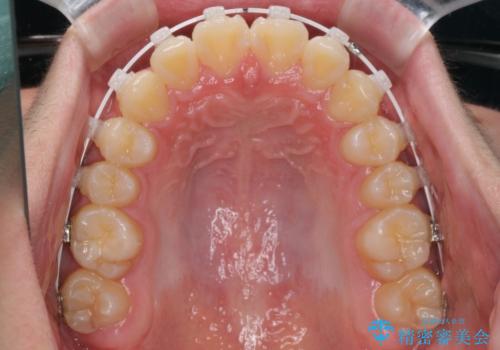

- 矯正装置

- 審美装置

- 1年3ヶ月

- 上下前歯のデコボコを改善したいとのことで来院された患者様です。

自己管理を減らしたいとのことで、ワイヤー装置による矯正治療を行うこととしました。